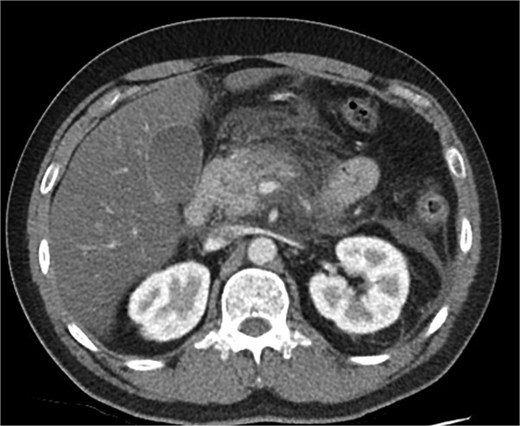

A 39-year-old male presented with one week of worsening epigastric pain radiating to the back, with vomiting, jaundice, and dark urine. His past medical history included depression and alcohol-related liver disease without cirrhosis. On admission he was afebrile, had a soft abdomen with epigastric tenderness worse on palpation, tachycardic, and normotensive. Initial investigations showed a lipase of 2600 U/L, C-reactive protein 238 mg/L, lactate 3.4 mmol/L, and bilirubin 100 μmol/L (Table 1). Abdomen and pelvic computer tomography (CT) demonstrated body and tail pancreatitis, fat stranding, portal vein thrombus, and early necrosis signs, with no choledocholithiasis (Figs 1–3).

Axial CT image demonstrating non-occlusive portal vein thrombus (depicted by arrow).